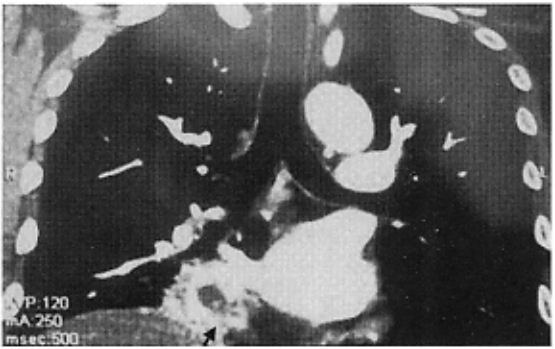

胸部CT+肺静脉成像:右下肺心缘旁团块状阴影,形态不规则,边界不清楚,最大径约3cm;增强后边缘强化,中央区无强化,与右下肺静脉关系密切(图)。支气管通畅,纵隔淋巴结无肿大。

图:胸部CT+肺静脉成像(上图为平扫,下图为增强),示右下肺心缘旁团块状阴影(箭头所示)与右下肺 静脉关系密切。